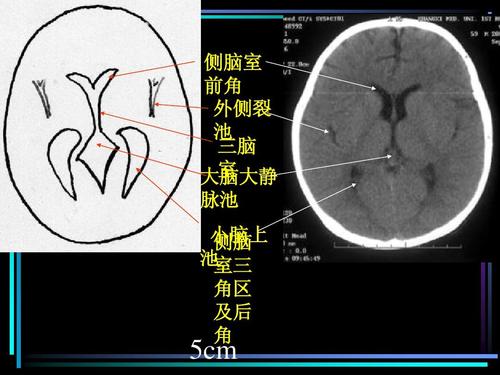

侧脑室解剖

侧脑室解剖,侧脑室在哪个位置图片

免费文档 所有分类 医药卫生 头颅ct解剖ppt 正常头颅ct解剖 侧脑室

侧脑室在哪个位置图片

侧脑室三角区图片

侧脑室三角区示意图

侧脑室解剖位置示意图

侧脑室解剖图

侧脑室三角区

侧脑室断层解剖图

侧脑室的解剖结构图

侧脑室三角区解剖图

侧脑室ct